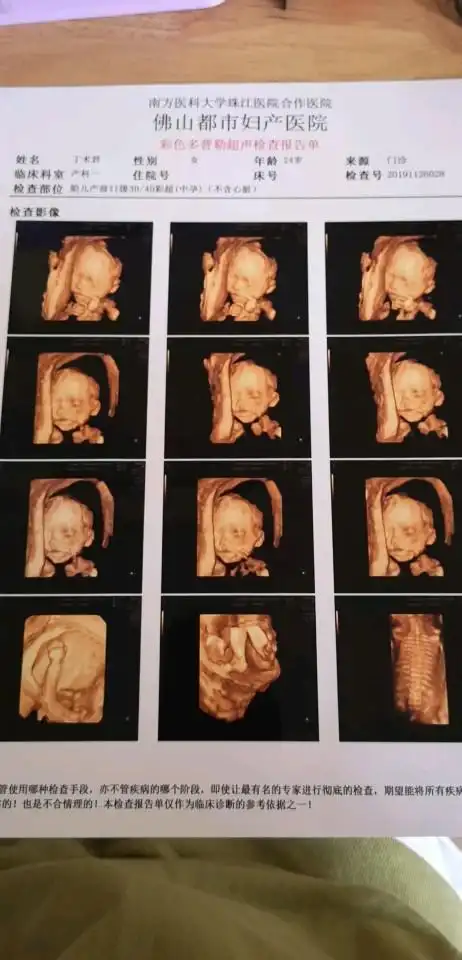

四维彩超图片,朋友们看看是女孩子是男孩子